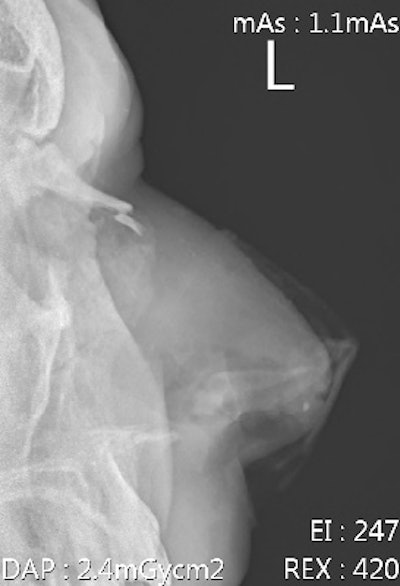

Hamstring strains and injuries are common in fast bowlers. Injuries of the hands/fingers such as avulsion fractures and dislocations are usually a result from a player catching the ball and are common. Rotator cuff injuries are often seen in fast bowlers and fielders, with labrum injuries commonly seen in fielders.

Additional forces are transmitted to the spine through the lower limb, while additional forces at the lumbo-sacral junction are caused by trunk hyperextension, lateral flexion, and twisting during the delivery stride. Outfield players (fielders) and bowlers do not wear any protective equipment, except close-in fielders, who wear helmets. The wicket keeper usually wears a helmet, gloves, and pads. The batsman is the best protected of them with helmet, gloves, and leg and forearm pads.